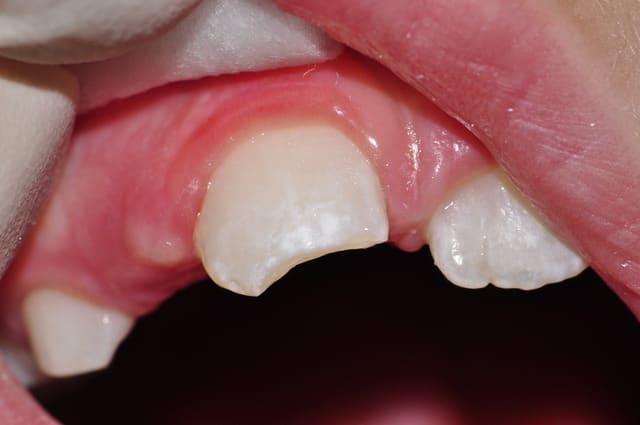

voila quelques traitements,modestes mais je suis encore jeune....

encore des radios,peut-etre assez moyen comme traitement...mais je vu pire...

les dernieres radios. patient en urgence ,abces... il voulait pas extraire la dent. j'ai lui bien explque et il a choisi de essayer de garder la dent. retrait,pas d'isolation avec la digue donc pas de tenon fibree,amalgam et screw post.traitement fait il ya 2 ans je crois.patient fidel de cabinet maintenent.

j'ai jamais utilise en roumanie l'amalgam et ca s'utilise pas du tout dans le cabinet du roumanie.